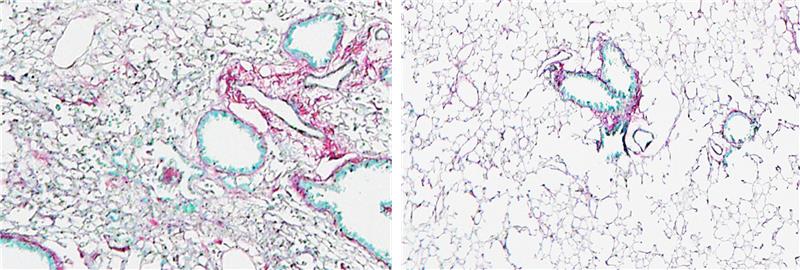

Lung tissue showing scarring in an induced fibrosis model (right); while WWP2 inhibition protects tissue structure from fibrosis (left) // Credit: Courtesy of Chen Huimei, Duke-NUS Medical School

65LAB has awarded US$1.5 million to Professor Enrico Petretto at Duke-NUS Medical School to advance a computational platform aimed at developing new antifibrotic drugs for lung and kidney diseases. The platform, called Systems Genetics, integrates AI and quantum computing to accelerate the discovery of first-in-class therapies for conditions with no effective treatment. Additional support from Duke-NUS’ LIVE Ventures will help bridge the path from lab to clinic.

“These compounds block a key fibrosis gene and showed a 50 per cent reduction in tissue scarring in pre-clinical studies.”

Professor Enrico Petretto